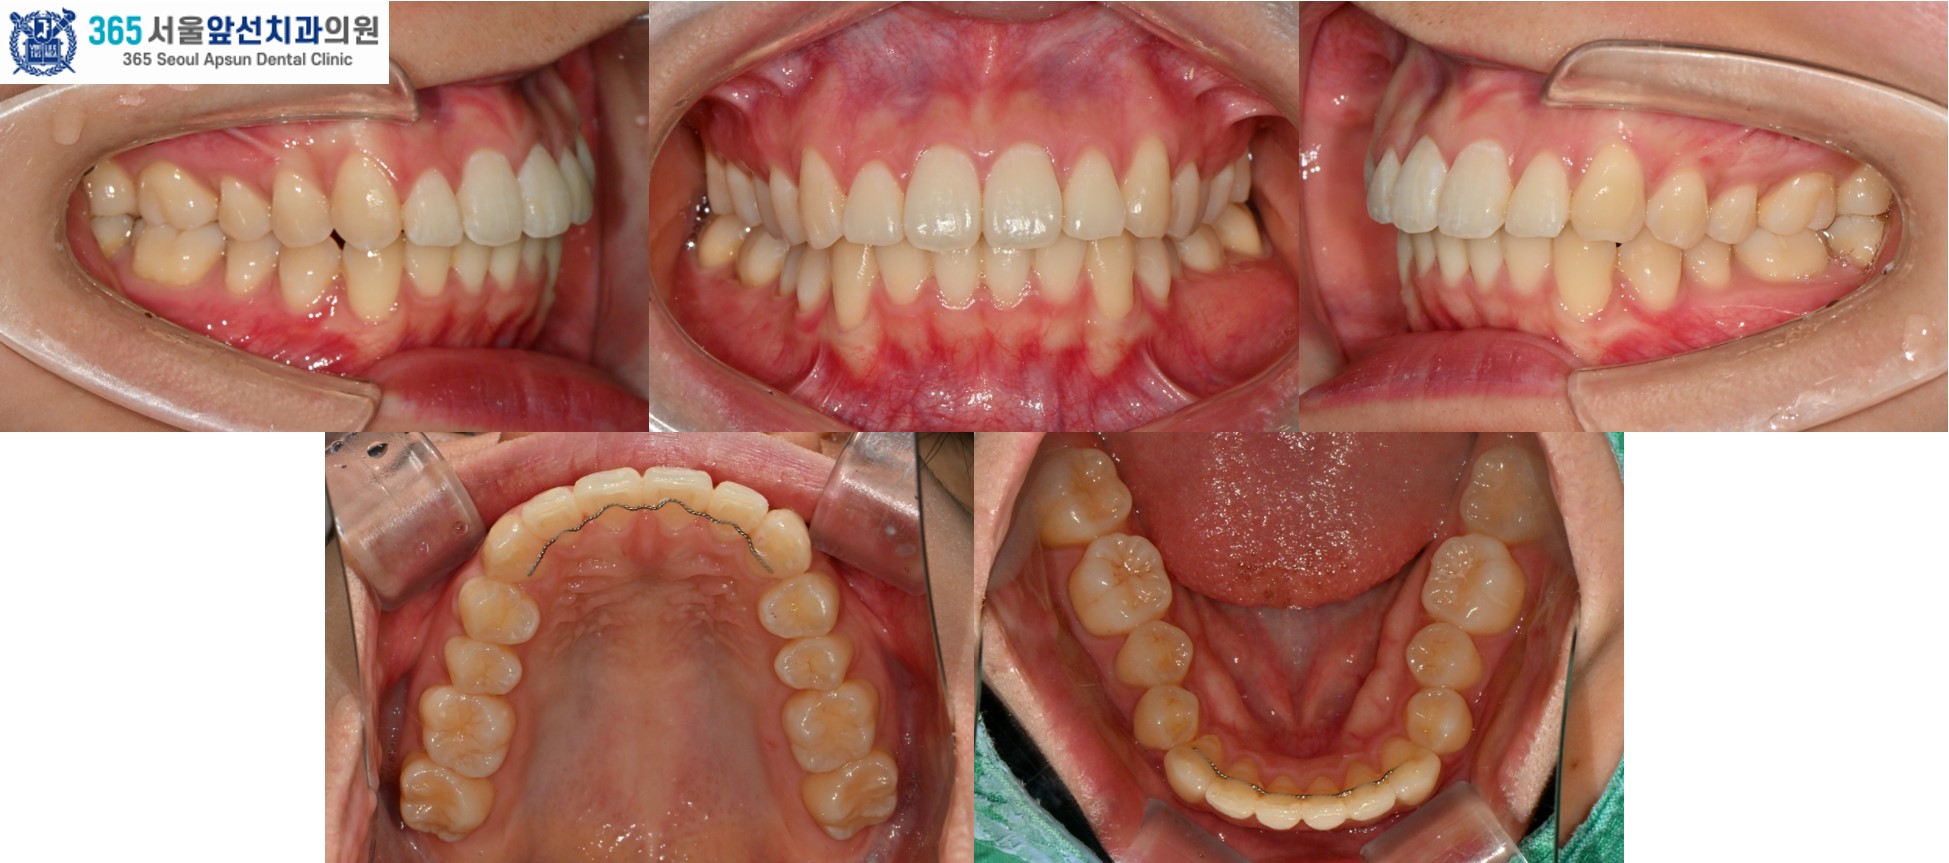

아랫니의 치열이 윗니의 치열보다 후퇴되어있는 2급 부정교합도 있었지만, 환자분은 2급 부정교합은 수정하지 않고 앞니의 치열만 가지런히 하기를 원하셔서 부분 교정으로 진행하였습니다. 이 경우, 2급 부정교합과 수평 피개는 잔존하게 됩니다. 부정교합의 정도에 따라, 치료계획을 좀더 간단하게 수정할 수 있습니다. 전체 교정과 부분 교정의 계획은 꼭 전문의와의 상담을 통해 결정하는 것이 좋습니다. ^^ (그림3) 촬영일자 2025.11.06.

치료 후의 모습입니다. 아랫니 치열은 약 5개월, 윗니 치열은 약 7개월의 치료기간이 소요되었습니다. 앞니의 치열이 가지런하게 배열되어 환자분도 만족하셨습니다. 미소 시 자연스럽고 단정한 인상으로 변화하였습니다. 앞니 부분 교정 증례의 치료기간은 4-9개월 사이로 정도에 따라 상이합니다. 부분 교정 관심 있으신 환자분들께서는 365서울앞선치과로 내원하셔서 교정 진단 받아보시길 바랍니다. 감사합니다!